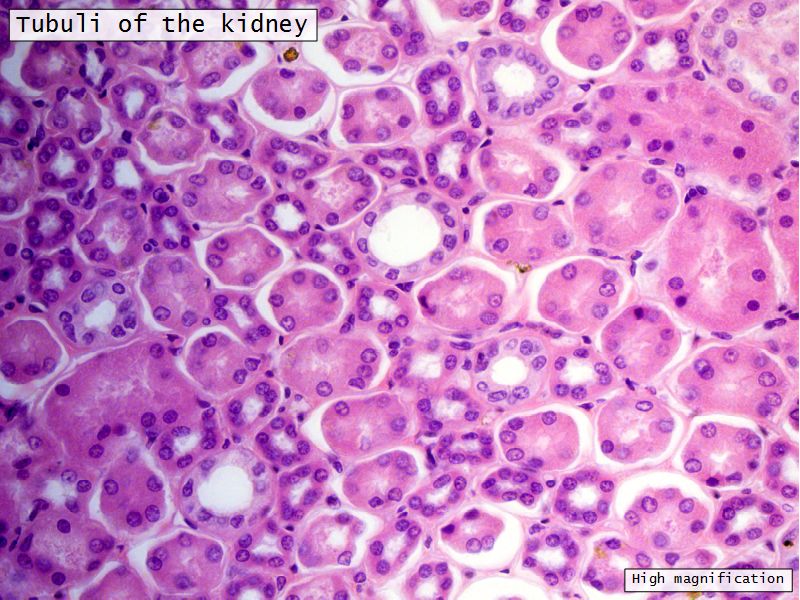

Appearance

- Cortex

- Renal corpuscles

- Convoluted tubules

- Medulla

- Loops of Henle

- Collecting tubules